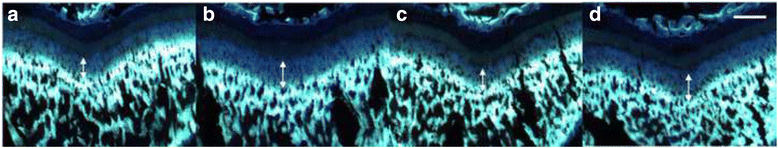

摘要:Yukmijihwangtang(YJT)是韩国传统药物用于治疗如头晕耳鸣等肾阴虚的症状,此外,也被认为滋养肾阴,已被用来治疗矮身材先天性缺陷。本研究评估YJT对大鼠骨骼纵向生长的影响。方法:雌性大鼠被随机分配到接受纯水组(口服一日两次;对照组)、重组人生长激素(rhGH;20μg/kg,皮下注射每天一次),或两个不同剂量的YJT(100或300毫克/千克,口服一天两次)。各组均给药维持4天。在2-4天,大鼠腹腔注射5-溴脱氧尿嘧啶(BrdU标记的;50毫克/公斤)用来标记增殖的软骨细胞。第3天腹腔注射盐酸四环素(20毫克/千克),能在生长板上形成荧光带,测量骨的纵向生长速度。应用免疫组织化学方法鉴定生长板中胰岛素样生长因子-1(IGF-1)和骨形态发生蛋白2(BMP-2)的表达。结果:相比于对照组,300mg/kg的YJT组骨生长率显著增加,而100mg/kg的YJT组骨生长率无显著增加。与对照组相比,重组人生长激素治疗组的软骨细胞表现出BrdU阳性细胞数显著增加,而300毫克/公斤YJT组无显著增加。此外,300毫克/千克YJT和rhGH组生长板的IGF-1和BMP-2表达水平较高。结论:YJT通过刺激软骨细胞增殖,增加局部IGF-1和BMP-2的表达增加骨骼纵向生长速率。基于这些发现,YJT可以作为治疗青春期生长发育迟缓的候选药物。关键词:yukmijihwangtang 生长板 骨骼纵向生长 重组人生长激素 背景:YJT已被用来治疗癌症、老年痴呆症、糖尿病、高血压、更年期综合征、肾炎、神经衰弱、神经症、帕金森病、系统性红斑狼疮、血小板减少性紫癜。YJT具有抗衰老、抗肿瘤、抗高血压、抗炎、抗骨质疏松、抗氧化剂和神经调节等药理作用。YJT被认为可以延缓学习和记忆的衰退,减少衰老过程和老年疾病,增强更年期雌激素活性。YJT已用于临床治疗肾阴虚症状如头晕、潮热、口干咽燥、盗汗、遗精、过度口渴和液体摄入,舌红苔少,脉冲过快。以前的实验研究表明,YJT通过调节与下丘脑-垂体-肾上腺轴有关的神经递质和激素的分泌,增强免疫功能以及通过刺激重塑过程来强化骨骼。YJT也通过改进突触可塑性增加认知功能和通过调节线粒体功能和抑制凋亡信号预防神经退行性疾病。在一个肥胖模型中、银捷通改善能量代谢和敏感性胰岛素和瘦素,反过来,抑制体重增长和内脏脂肪堆积。此外,YJT减少前列腺增生。由于有YJT对骨生长的影响的相互矛盾的报道,本研究评价了不同YJT浓度对青春期雌性大鼠的影响。YJT剂量100毫克和300毫克/公斤是因为这些浓度对骨的生长与对照组相比有显著影响。本研究中的一组大鼠接受GH作为阳性对照,因为GH影响出生后的最终身高,在青春期的生长突增过程中起着多种作用。此外,GH基因在大鼠体内的过度表达显著增加了机体和器官的生长。这也表明GH促进青春期大鼠胫骨生长和体重增加。因此,本研究以青春期雌性大鼠作为实验动物,对胫骨的生长进行了评估。在这项研究中,纵向骨生长是通过评估胫骨生长板的长度增加超过48小时。生长板5'-溴脱氧尿苷(BrdU)阳性细胞数量验证软骨增生,免疫组织化学法检测骨形态发生蛋白2(BMP-2)和胰岛素样生长因子-1(IGF-1)的表达,其与生长板的骨生长有关。方法:动物及管理:研究包括32只雌性SD大鼠(4周龄)重量70±10克。动物体重分为四组(30-40 g,40-50 g,50-60 g,60-70 g)。用均匀重量分配法随机分为八笼(4鼠/笼),随机分为四组。动物被安置在控制条件下(温度23±2°C,相对湿度55±10%; 07:00-19:00灯光照射,可自由采和饮水)。经过5天的驯化,各组均连续给药4天。对照组给予蒸馏水,口服一天两次,对照组皮下注射20μg/kg重组人生长激素(rhGH)一天一次,而两YJT组100或300毫克/公斤口服给药,一天两次。口服给药在09:00至21:00,注射给药时间为09:00。给药结束后处死动物。骨纵向生长测量:为探讨YJT对骨骼纵向生长的影响,四环素作为标记物标记胫骨表面的骨线,四环素在紫外光照射下是发荧光的。通过测量四环素形成的荧光线与生长板骨骺端部之间的距离来评估纵向骨生长的速率。要做到这一点,在实验的第3天所有大鼠腹腔注射(ip)盐酸四环素(20毫克/公斤)。在第2-4天,大鼠腹腔注射BrdU(50毫克/公斤)标记增殖的细胞,第5天所有的动物用乙醚麻醉处死。解剖胫骨被固定在4%多聚甲醛48小时,然后在10%乙二胺四乙酸溶液中浸泡24小时进行脱钙。在30%蔗糖溶液中浸泡1天脱水后,每个骨样品纵向剖面切割厚度40μm。注射四环素后,在骺板和荧光板上形成的荧光带位于四环素荧光显微镜下形成可见的荧光带。从荧光带隙的三个不同部分获得平均值,使用ImageJ软件进行测量和计算骨的生长。生长板BMP-2和IGF-1的测定:组织切片在0.1 M磷酸缓冲液(PBS)洗涤两次, 1% Triton X-100 15 min洗涤两次,然后用溶于PBS的 0.5%牛血清白蛋白(BSA)15分钟洗涤两次。切片用山羊BMP-2一抗和兔IGF-1一抗(1:200)室温条件下孵育过夜。24小时后,切片,用含 0.5% BSA的PBS洗两次,与生物素标记的抗羊二抗(1:200)或生物素标记的抗兔二抗体(1:200)孵育1小时。用PBS洗两次15分钟后,切片用亲和素-生物素-过氧化物酶复合物(1:100)在室温下孵育1 h。PBS冲洗后,切片用DAB染色。用PBS洗涤,然后用50, 75, 95,100%乙醇和二甲苯溶液进行脱水。镜检。结果:YJT对骨纵向生长速率的影响:以生长板和四环素形成条带带之间的三个不同的地点获得平均值评估YJT对骨生长的影响。超过48小时的骨生长程度被转化为每日增长率。与对照组相比,300毫克/千克YJT和rhGH组对骨骼纵向生长有一个显著的加速。然而, 100毫克/千克YJT组与对照组比较,骨生长率没有显著差异。YJT对软骨细胞增殖的影响:在软骨细胞中观察到BrdU标记细胞。rhGH组BrdU阳性细胞数明显高于对照组,但300毫克/千克YJT组BrdU阳性细胞与对照组相比差异不显著。YJT对BMP-2和IGF-1表达的影响:用免疫组织化学方法观察生长板三个主区BMP-2和IGF-1的表达情况。所有组,在增生和肥大区的细胞质中BMP-2和IGF-1染色最明显。相比于对照组,300毫克/公斤YJT明显增加BMP-2和IGF-1在增殖区和生长板的表达。此外,rhGH组BMP-2和IGF-1的表达比对照组和YJT组高。结论:目前的研究表明,在一定浓度下,YJT通过增加BMP-2和IGF-1在增殖和肥厚的生长板带的表达促进骨骼纵向生长的速度。虽然,YJT有治疗身材矮小的成本效益和安全治疗潜力,但仍需要进一步的实验来进行验证该中草药的活性成分。